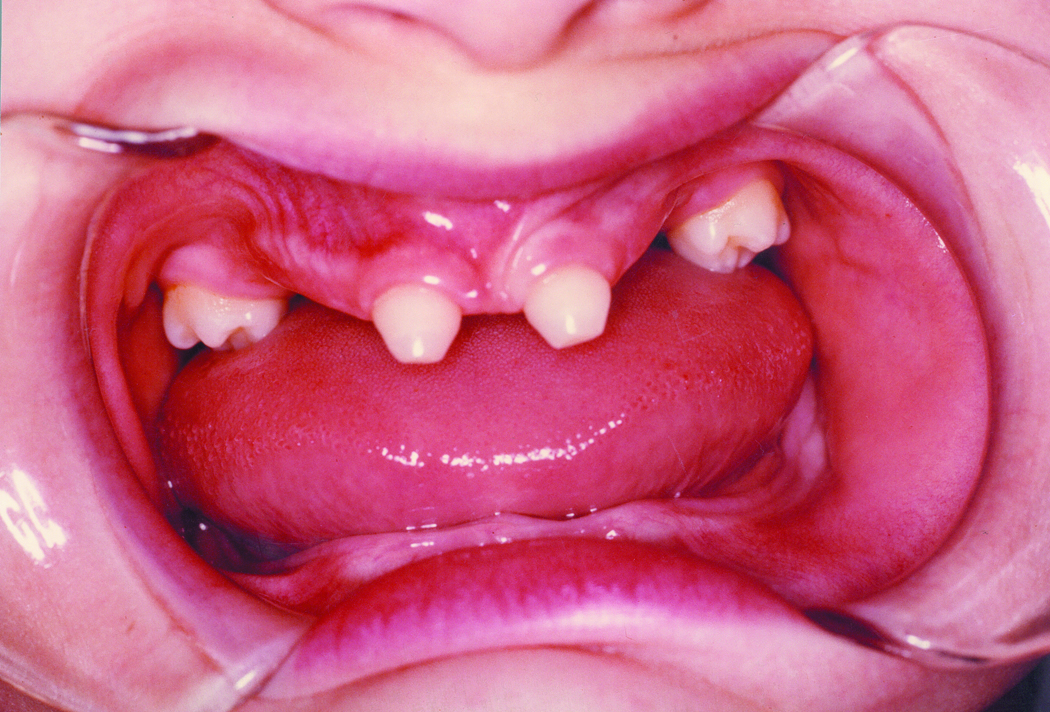

Ectodermal Dysplasia Teeth

Dental Symptoms Ectodermal Dysplasia NFED Orthodontic Treatment Ectodermal Dysplasia The treatment of a 10. The feasible treatment option was. The objective of this systematic review was to determine the orthodontic and dentofacial orthopedic. We included articles describing patients with any type of ectodermal dysplasia who received orthodontic or dentofacial orthopedic treatment. In ed patients with anodontia,. Treatment options were discussed with dentists of multidiscipline and patient’s father. Preservation of. Orthodontic Treatment Ectodermal Dysplasia.